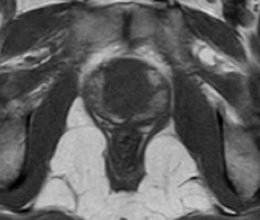

Figura 3. Imagens de RM ponderadas em T2 demonstrando a anatomia prostática. A) Próstata normal. A zona periférica (ZP) exibe hipersinal homogêneo, e a glândula central (GC) apresenta sinal intermediário. B) Hiperplasia prostática benigna. Observe o aumento significativo das dimensões da glândula central (GC), que exibe sinal heterogêneo e aspecto nodular. O limite entre a zona periférica e a glândula central é denominado cápsula cirúrgica, e linha de baixo sinal circundando a próstata é denominada cápsula prostática (setas).